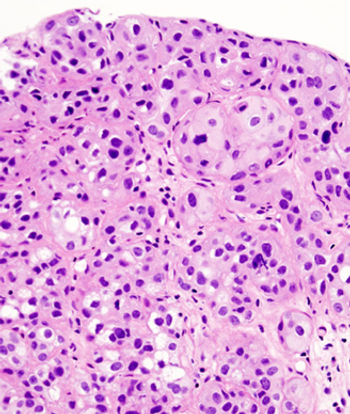

A 76-year-old woman with a history of dementia, hypertension, type 2 diabetes mellitus, and newly diagnosed squamous cell carcinoma of the urinary bladder was referred to Indiana University Medical Center after 3 to 4 weeks of hospitalization at two other hospitals.